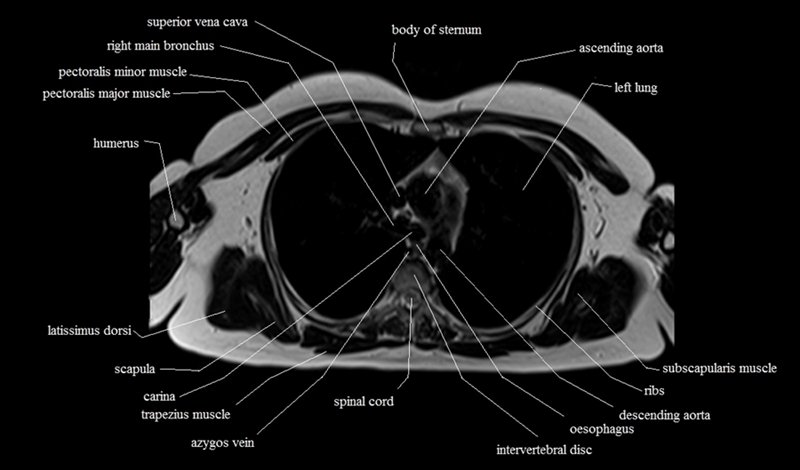

MRI Axial Cross Sectional Anatomy of Chest

This MRI chest (thorax) axial cross sectional anatomy tool is absolutely free to use. Use the mouse scroll wheel to move the images up and down, or alternatively, use the tiny arrows (→) on both sides of the image to navigate through the images. For a more detailed view, double-click the image to view it in full screen, and use the menu in the top right-hand corner to view individual slides or play them in a loop.